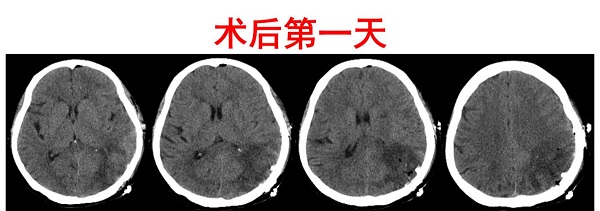

姚阿姨年龄较大、病情复杂,如果采用“脑洞大开”的治疗方式,无疑是在挑衅死神。为减少手术创伤,同时达到快速清除血肿的目的,谢国强主任团队选择神经内镜辅助下脑内血肿清除术。以“技术+医术”的双重保障,依据影像数据,科学精准规划手术路径,通过神经内镜的“天眼”,一滴不漏、一丝不伤地将血肿清除,手术时间短、创口小、过程顺利、效果良好。在复查的头颅CT中可以清晰的看到,血肿清除的非常干净。

脱险靠治,康复靠养,面对危重的病情,姚阿姨后期的救治、护理与营养支持就显得更加重要。神经重症监护室医护团队以专业的处理经验,为姚阿姨的身体康复保驾护航,结合姚阿姨身体情况、特殊需求,为她量身制定了相应的诊疗方案和护理计划,安排专人陪同,一对一精细服务。经过及时的治疗和精心的护理,姚阿姨的病情逐渐稳定,失语症状较查体时改善明显,右侧肢体活动水平也逐渐恢复至正常人状态,生活基本可自理。一辈子辛勤操持、闲不下来的姚阿姨,也能继续在家做一些力所能及的家务活。出院时,姚阿姨及其家人也对一路帮助和陪伴自己的医护人员表达了赞扬和感谢。